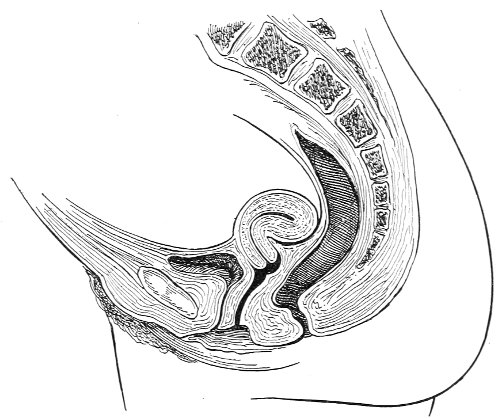

Vaginal and Bimanual Examination.—Having examined and noted the condition of the external genitals, the physician should next proceed to examine the vagina. The index finger of the right or the left hand should be gently introduced into the vagina. The condition of the vaginal walls, and the direction, consistency, form, etc. of the vaginal cervix, may be determined. The shape and size of the os uteri should be noted. The ulnar edge and the tips of the fingers of the other hand should then be placed upon the abdomen, immediately above the symphysis pubis, and gently pressed backward and downward toward the vaginal finger 24 (Fig. 2). In this way the various pelvic organs, the uterus, Fallopian tubes, ovaries, and ureters, may be palpated between the two hands, and their position, size, shape, and consistency may be determined. Such an examination is, of course, made much more easily in a thin woman than in a fat one. A thin woman a few weeks after labor may be examined most easily, on account of the relaxation of the abdominal and vaginal walls.

Fig. 2.—Bimanual examination.

This is called the bimanual method of examination, and the student will find that as he acquires practice in this method he will gradually depend less upon examination by the uterine sound and the speculum, and will rely altogether upon his sense of touch, his ability to palpate.

In making the bimanual examination the structures 25 should be palpated methodically in order. The vaginal finger notes the condition of the cervix uteri. If the fundus be in the normal position, the uterus can then be taken between the abdominal hand (upon the fundus) and the vaginal finger (upon the cervix) (Fig. 3). The shape, size, mobility, and consistency are noted. The vaginal finger is then passed anteriorly and laterally toward either uterine cornu, while the abdominal fingers pass over to the posterior aspect of the same cornu. The ovarian ligament and the proximal end of the Fallopian tube may thus be felt. Passing farther outward, the whole of the tube and the ovary may be examined. The same procedure is then applied to the opposite side.

Fig. 3.—Bimanual examination; median sagittal section of the pelvis.